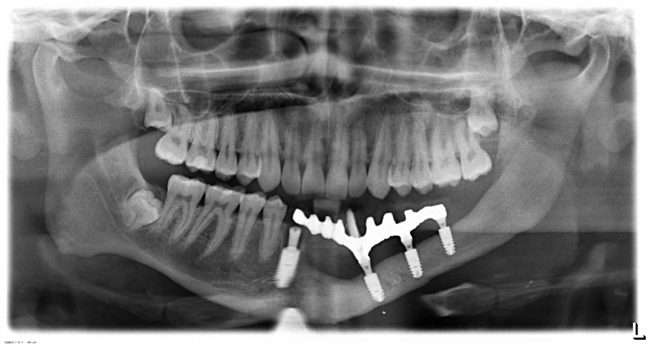

Не нужно расстраиваться! Базальная имплантация — это поправимо.